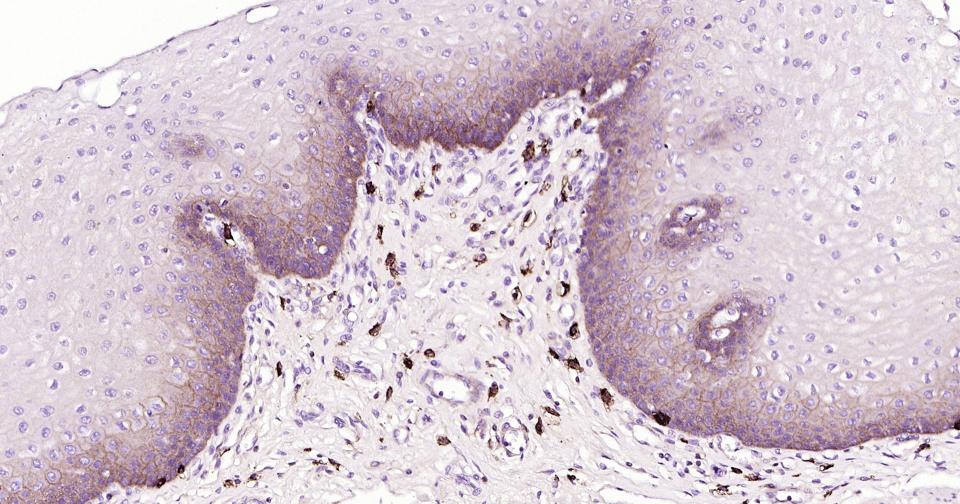

| IHC-P | Human | 1:100-500 | |